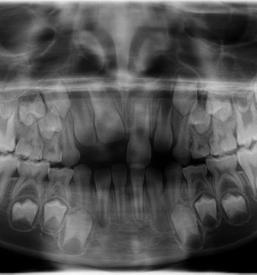

Svojim pacientom nudimo dober RTG zob v Ljubljani, center, kjer se nahaja naša ordinacija. Nudimo vam varno in natančno slikanje zob, ki je odločilnega pomena za nadaljnjo zdravljenje in zobozdravstveno obravnavo.

Pri svojem delu uporabljamo le najboljšo opremo, ki zagotavlja, da je RTG zob, ki ga opravljamo v Ljubljani, center, povsem varen, učinkovit, rezultati pa hitri in nazorni.

Rezultate, ki jih prinaša naš dober RTG zob v Ljubljani interpretirajo strokovnjaki in na podlagi slike določijo diagnozo in nadaljnjo zdravljenje, ki je potrebno za doseganje optimalnega stanja.